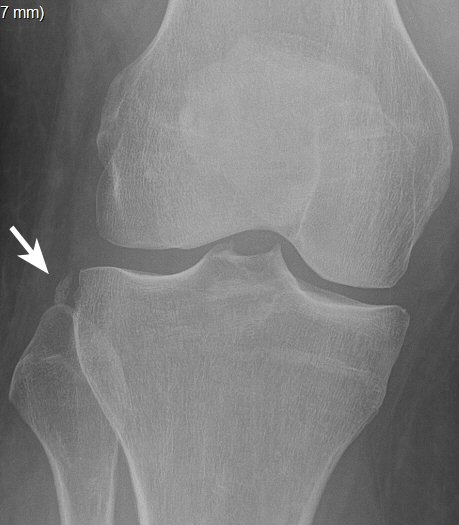

Segondfraktur: avulsionsfraktur lateralt av laterala tibiakondylen, är ofta associerad med ruptur av främre korsbandet.

Segondfraktur i högerknä